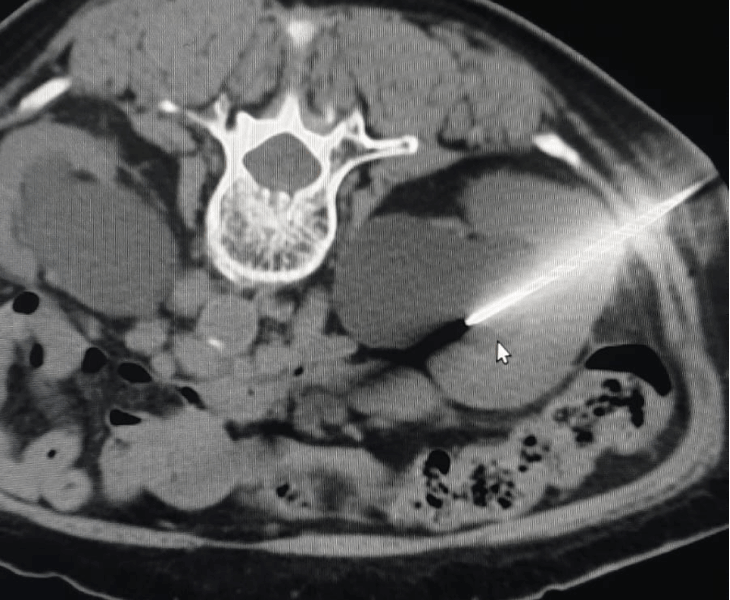

CT‑Guided Pelvic Biopsy

Accurate tissue sampling from deep pelvic lesions with CT guidance.